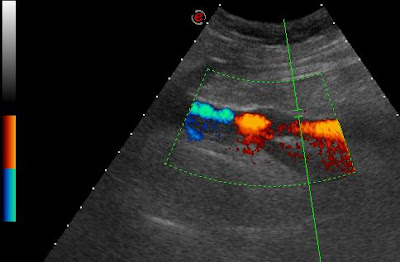

| hasonló megjelenés UH vizsgálattal axialis… |

| …és coronalis síkban |